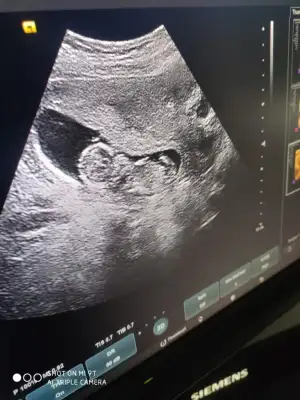

Erkek12 haftalık bana da bakabilir misiniz![]()

Diğer taraftaki konumda yazdim erkek gibi sanki tekrar USG paylasin12 haftalık bana da bakabilir misiniz![]()

12 haftalık USG bu çok teşekkür ederimDiğer taraftaki konumda yazdim erkek gibi sanki tekrar USG paylasin

Başka USG paylaşın12 haftalık USG bu çok teşekkür ederim![]()